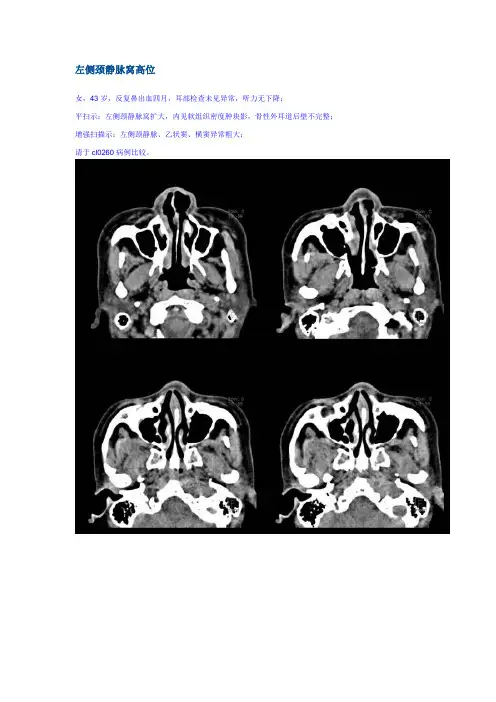

左侧颈静脉窝高位女,43岁,反复鼻出血四月,耳部检查未见异常,听力无下降;平扫示:左侧颈静脉窝扩大,内见软组织密度肿块影,骨性外耳道后壁不完整;增强扫描示:左侧颈静脉、乙状窦、横窦异常粗大;请于cl0260病例比较。

二:高位颈静脉球:是一种先天性变异;可表现为如本例:颈静脉窝扩大,内见软组织密度影(血管影),颈静脉窝边缘骨质光滑, 无破坏表现采用动态ct增强扫描或行颈静脉造影可以明确诊断.颈静脉孔综合征颈静脉孔综合征常由后颅窝肿瘤导致(例如脉络膜瘤)。